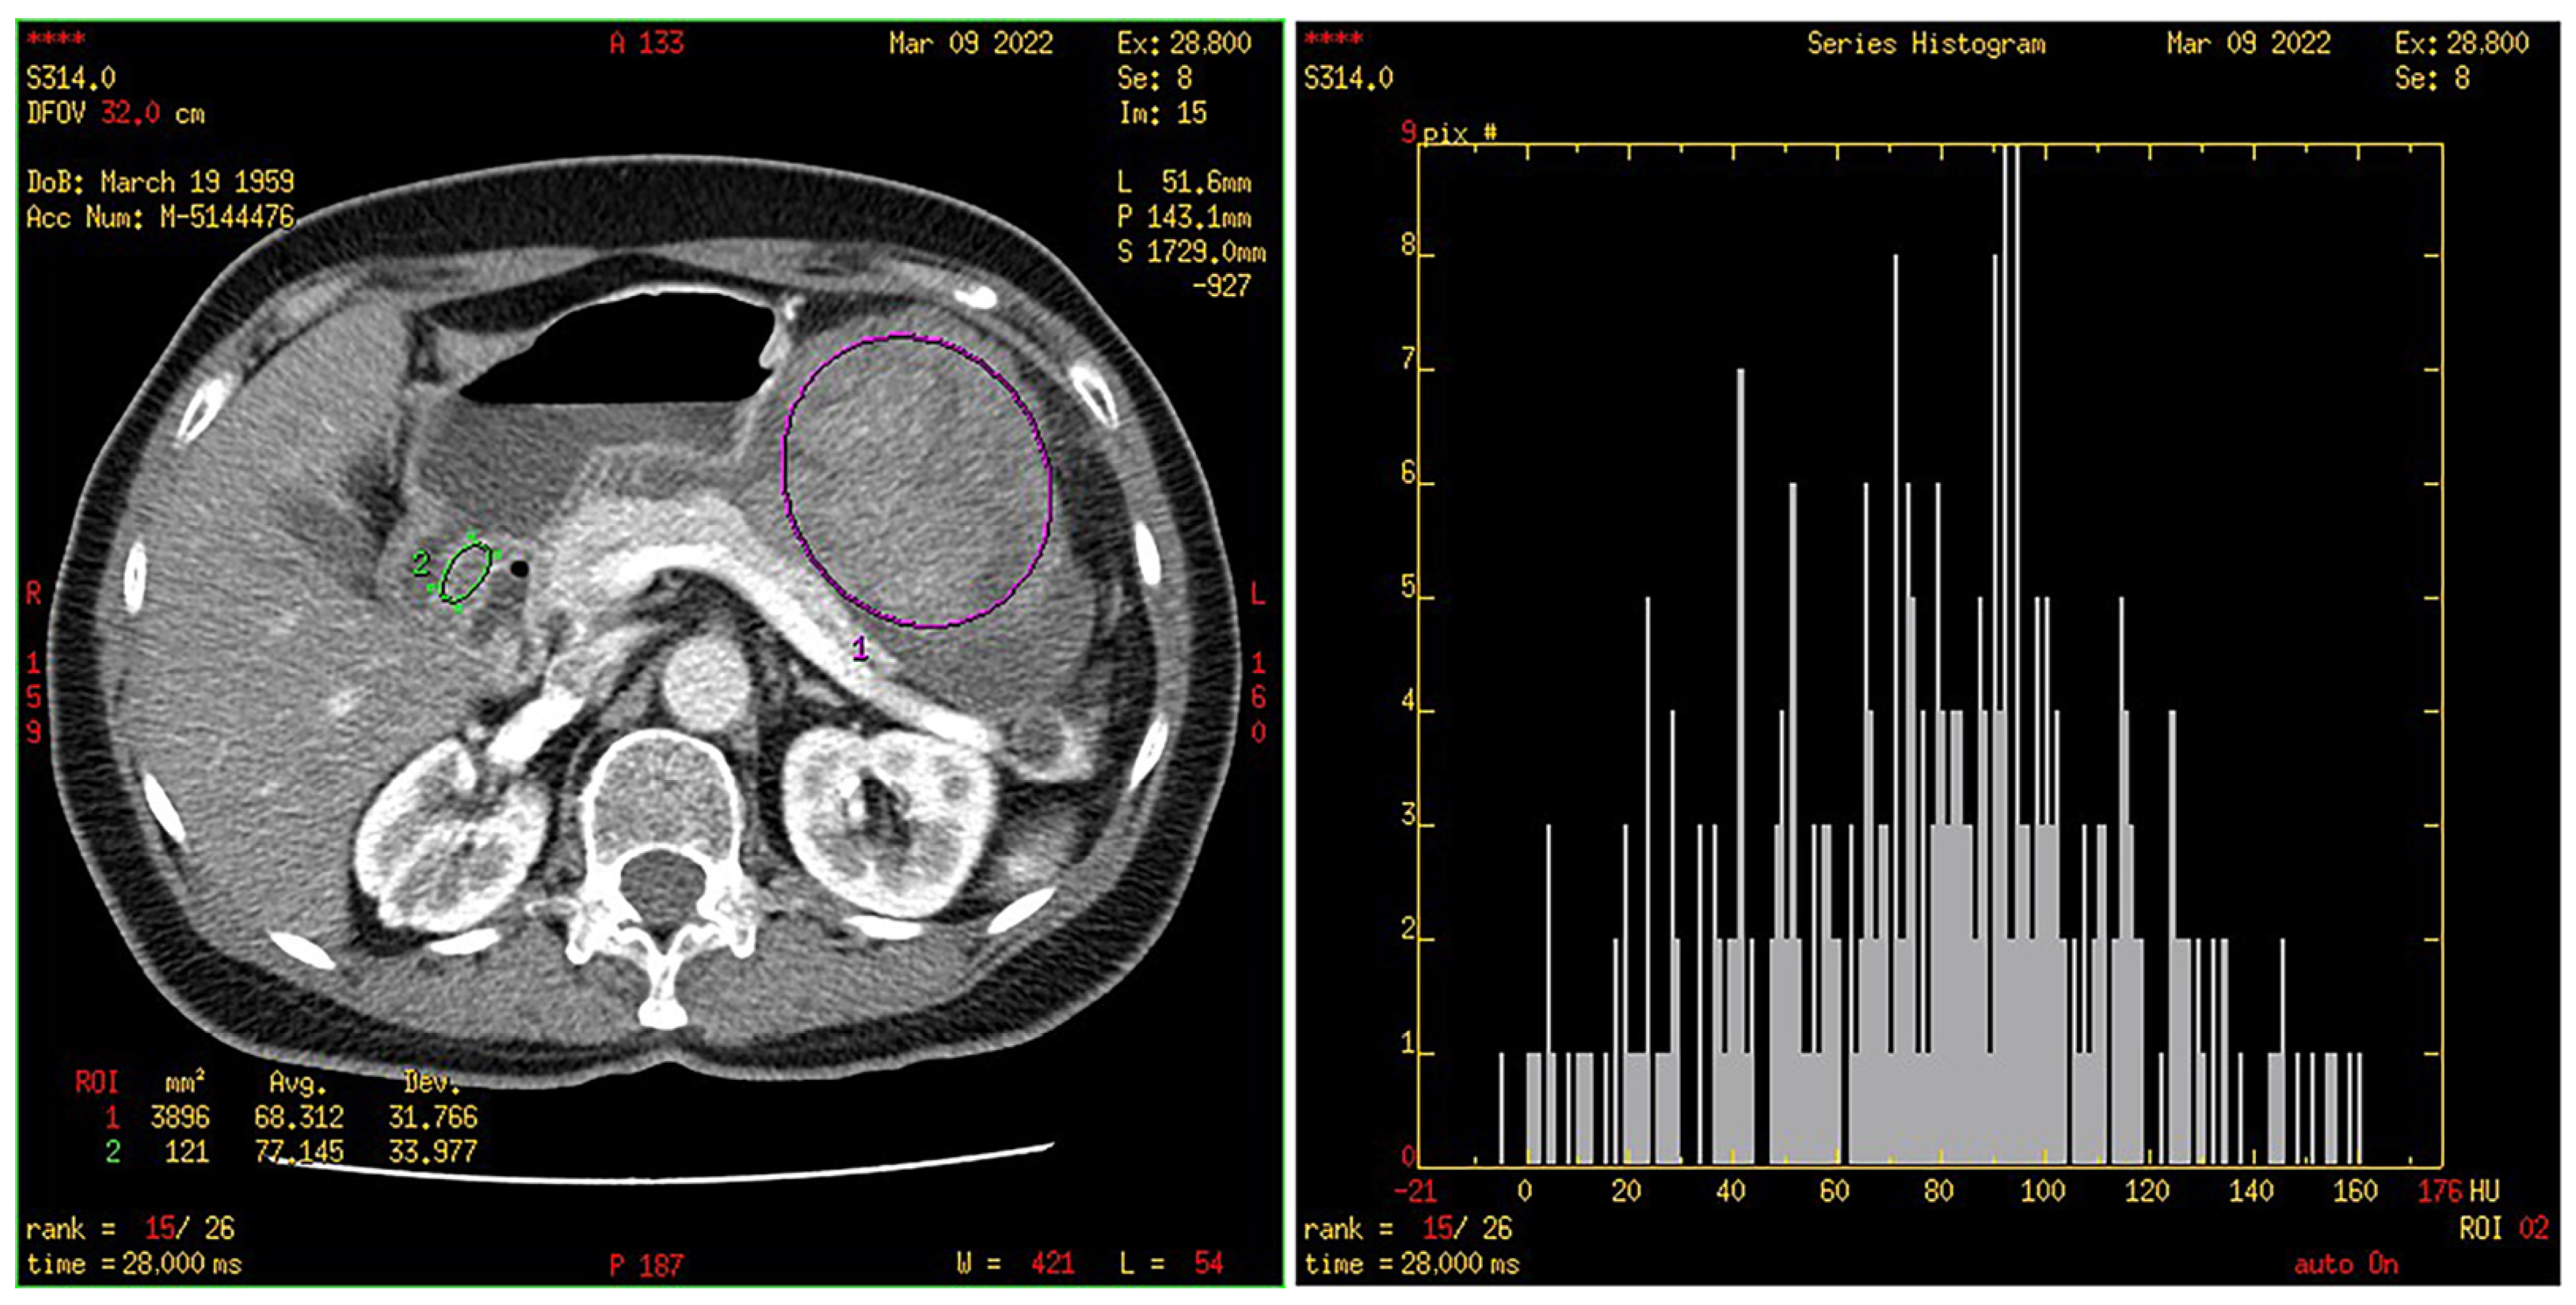

2.4. CT Texture Analysis

3.4. Histogram Parameters in HR and LR Group